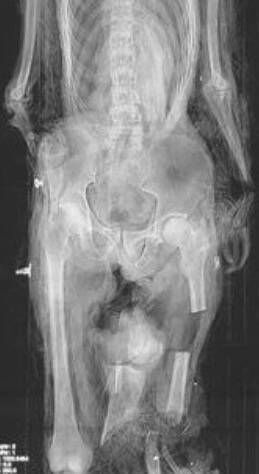

Duncan MacPherson went missing without a trace in August 1989, right before he was due to sign for Dundee’s Tayside Tigers. The 23-year-old’s remains were located 14 years later exhibiting several fractured bones and a crushed leg, frozen inside a glacier within the Austrian Alps, according to The Courier.

He had been encased in melting snow and ice in the middle of a heavily used ski slope in Neustift. Officials claimed he perished after falling into a crevasse, but a Canadian forensic anthropologist contended this did not explain the arrangement of fractured bones.

She suggested there had also been contact with a sizable piece of machinery, and the MacPhersons alleged Austrian authorities actively endeavored to prevent the truth from emerging.